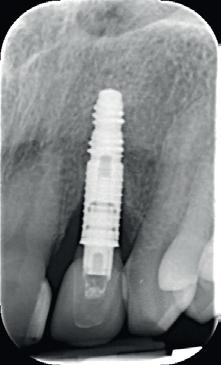

5. Implantaten geplaatst op geleide van een boorsjabloon; botopbouw met sinuslift volgens de GBR-techniek en Caldwell Luc methode; materialen: Oragraft & BioOss, Ossix membr, hyaluronzuur. In de BK is gekozen voor Bego implantaten (Bego SC en RSX 3,75x 11,5 & 13mm).

6. In het front zijn Bego 3,25mm

implantaten geplaatst terwijl in de zijdelingse delen voor een bredere diameter (3,75 & 4,1) is gekozen, met lengte 8,5 en 10mm.

7. OPT na abutmentchirurgie 6 maanden later. De integratie van de implantaten met de botopbouw & sinusliften verloopt voorspoedig.